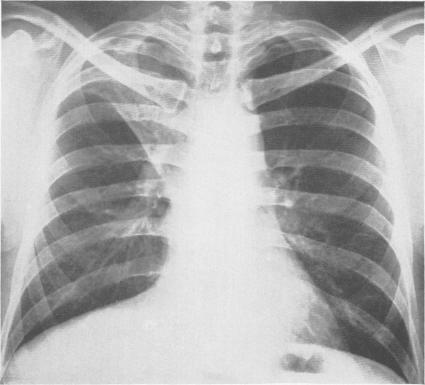

LOBECTOMY FOR PULMONARY TUBERCULOSIS.

Ann Surg. 1943 May;117(5):641-69. doi: 10.1097/00000658-194305000-00001.